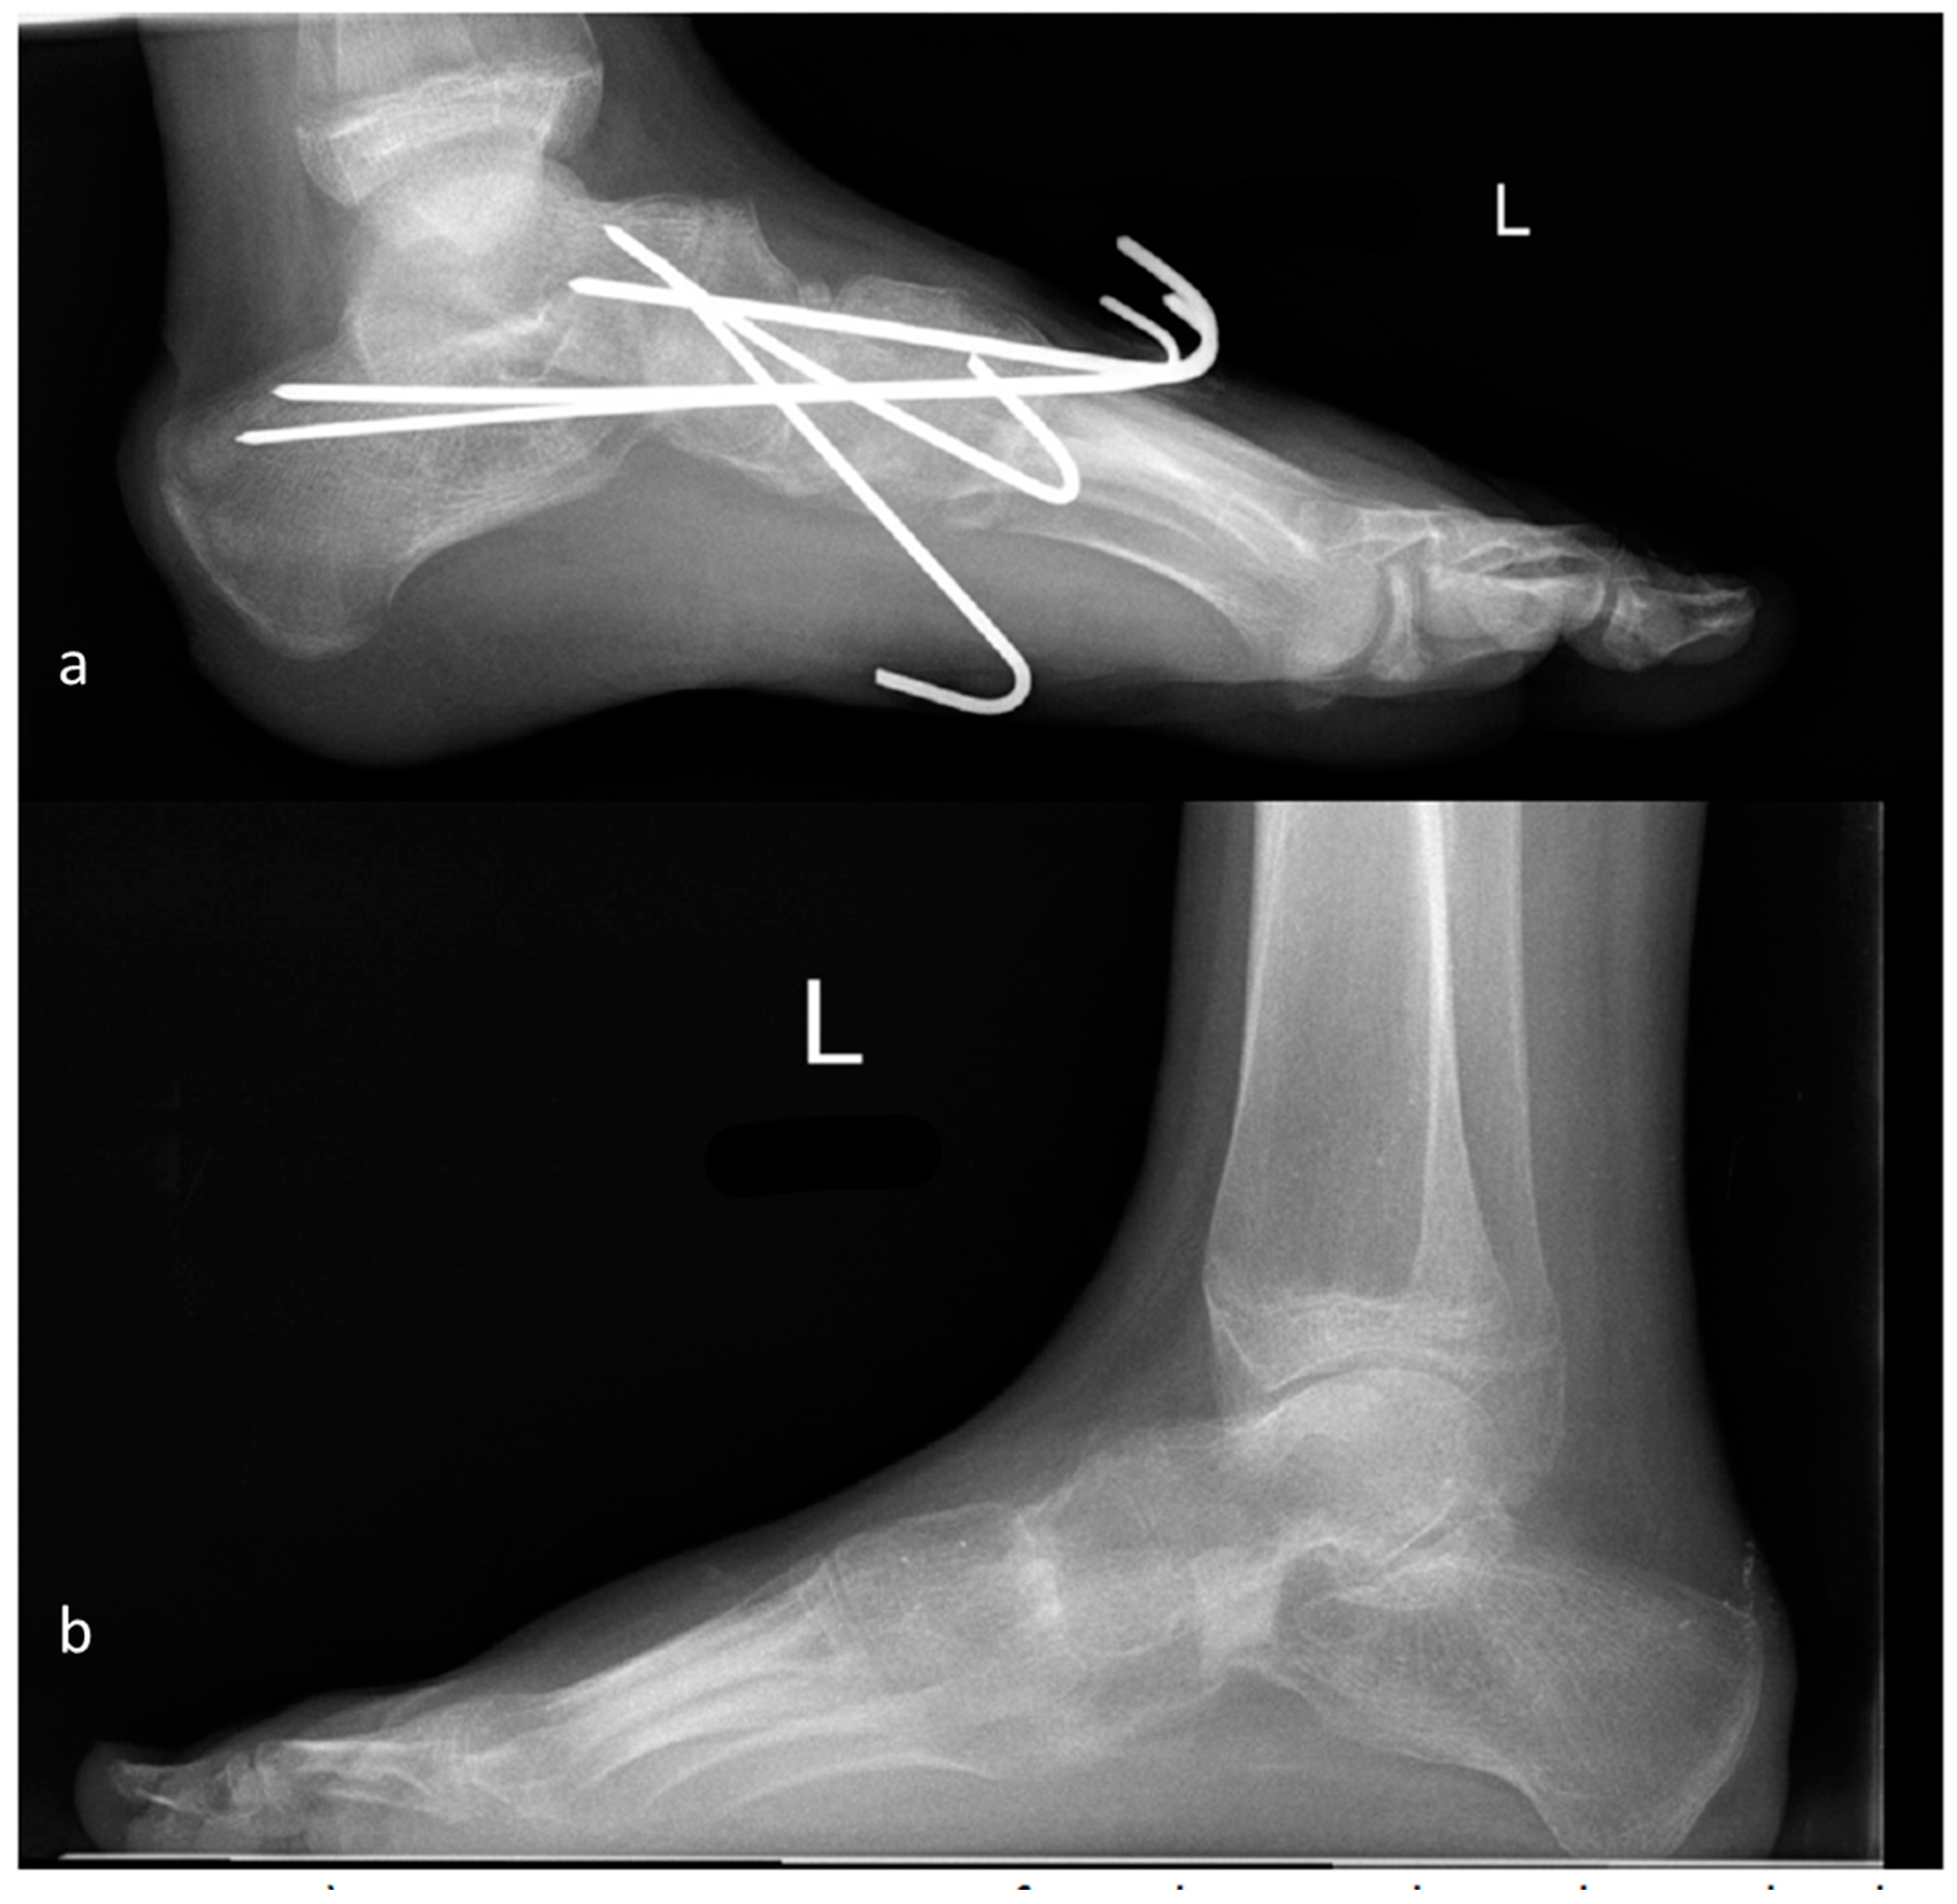

2.1. Operative Procedure

2.4.1. Modified Evans Procedure

2.4.2. Calcaneocuboid Distraction-Fusion

2.4.3. Grice Procedure

2.4.4. Triple Fusion